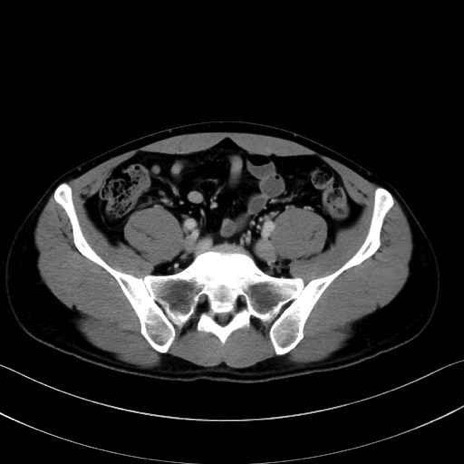

2. 腸腰筋群と骨盤底筋

大腰筋 (Psoas major)

腸骨筋 (Iliacus)

肛門挙筋 (Levator ani)